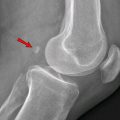

Rendgenski snimci pokazali su kako je dodatno oko kod zmije bilo funkcionalno kao i druga dva.